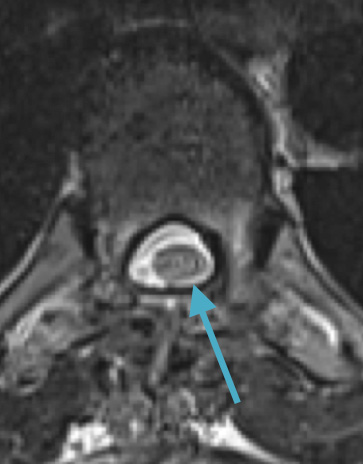

Preoperative MRI T1w demonstrating a large enhancing tumor (red arrow) causing severe cord compression and displacement (blue arrow)